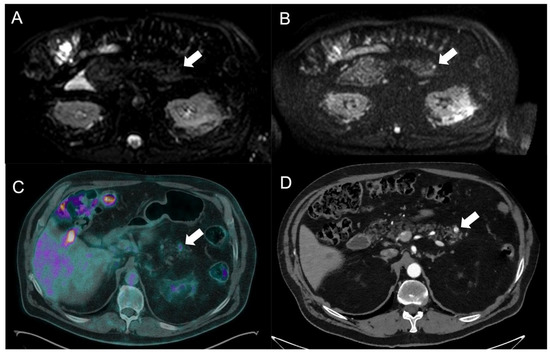

2.3.2. Magnetic Resonance Imaging

3.2. Liver Metastases